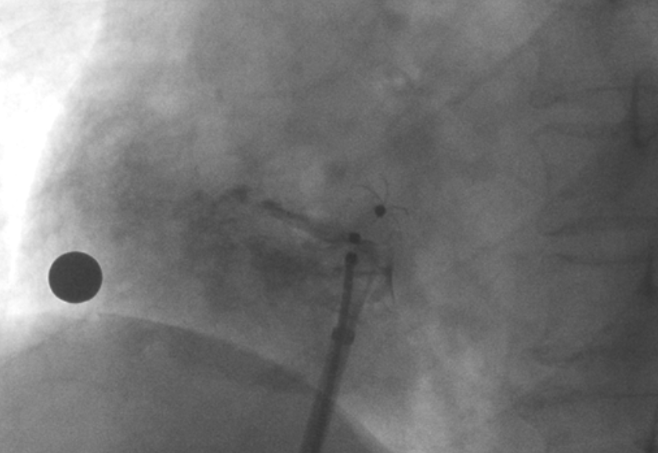

術中造影顯示患者為PFO且長隧道型,目前市場上已商業(yè)化的PFO封堵器難以滿足該患者解剖結(jié)構封堵需求。迪創(chuàng)醫(yī)療自主研發(fā)的OmniSeal PFO封堵器自適應性雙盤貼合設計能廣泛適應不同PFO隧道長度的解剖結(jié)構和形態(tài),其雙盤外包覆式阻流和隧道內(nèi)填充阻流相結(jié)合的雙重阻流設計,可為此患者實現(xiàn)有效封堵。與此同時,OmniSeal首創(chuàng)的完全可穿刺式設計,也為此患者最大程度地保留了房間隔區(qū)域穿刺通道,以實現(xiàn)全兼容未來可能的左心系統(tǒng)二次介入術。術終造影和心臟超聲顯示封堵完全、效果良好。作為OmniSeal的首例臨床應用,本次手術的順利完成和優(yōu)異效果充分體現(xiàn)了產(chǎn)品的設計創(chuàng)新優(yōu)勢。

造影顯示PFO封堵完全,無殘余分流, 試驗器械充分舒展并貼合良好